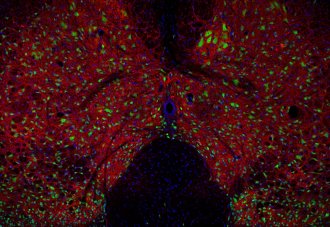

IHC: 1 : 500 gallery

Immunohistochemistry (IHC) on 4% PFA perfusion fixed tissue with 24h PFA post fixation. Immunoreactivity is usually revealed by fluorescence or a chromogenic substrate. Some antibodies require special fixation methods or antigen retrieval steps. For details, please refer to the ”Remarks” section.

GLYT 2 shows an axonal localization and is mainly expressed in spinal cord, brain-stem and cerebellum.